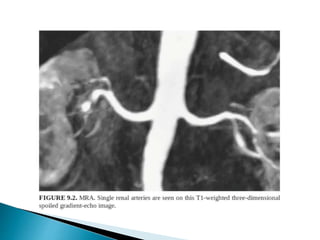

Transplant artery stenosis with MRA.

 CT is the preferred imaging due to better spatial resolution

and sensitivity to vascular calcifications and renal stones.

 CTA >> MRA

1. Distinguishing single/two main renal arteries.

2. Anatomy and to identify the point at which first branch

occurs.

3. Renal venous anatomy,

4. Tiny polar accessory arteries.